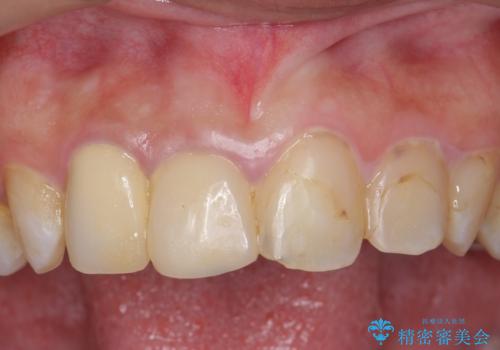

手前側の歯は前から見えるため、セラミックの詰め物で治療しました。

今後の虫歯予防に、治療と合わせて歯磨き指導も行っているため、清掃状態も大きく改善しています。